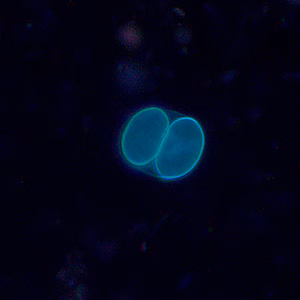

Both sporulated oocysts (containing two sporocysts) and individual sporocysts can be passed in stool

. Sporocysts contain four sporozoites and a refractile residual body. Sporocysts ingested by the intermediate host (cattle for S. hominis and pigs for S. suihominis) rupture, releasing sporozoites. Sporozoites enter endothelial cells of blood vessels and undergo schizogony, resulting in first-generation schizonts. Merozoites derived from the first-generation invade small capillaries and blood vessels, becoming second-generation schizonts. The second generation merozoites invade muscle cells and develop into sarcocysts containing bradyzoites, which are the infective stage for the definitive host

Sarcocystis oocysts in wet mounts viewed under ultraviolet (UV) microscopy.

For intestinal sarcocystosis caused by S. hominis and S. suihominis, diagnosis is made by the observation of oocysts or sporocysts in stool. They are easily overlooked as they are often shed in small numbers. Also, the two species cannot be separated by oocyst or sporocyst morphology. When humans serve as dead-end hosts for non-human Sarcocystis spp., diagnosis is made by the finding of sarcocysts in tissue specimens.